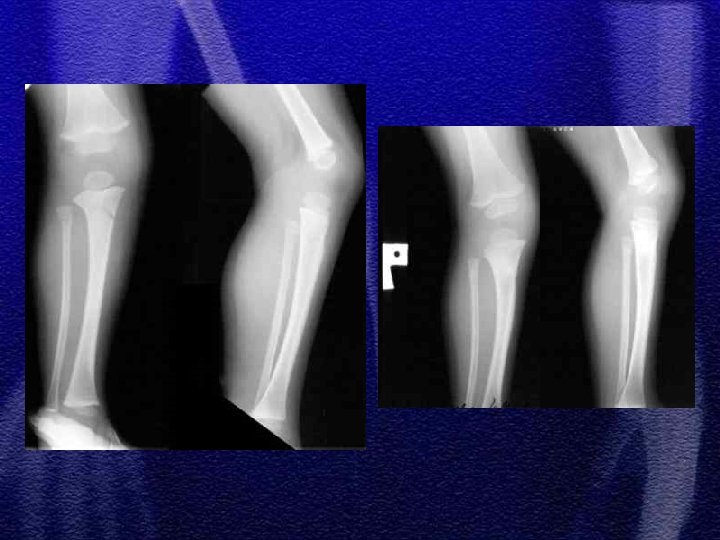

§ Dotyczy najczęściej chłopców w wieku 4 -10 lat § Złamanie występuje najczęściej w środkowej części trzonu § Dziecko jest we wstrząsie z powodu bólu i dużej utraty krwi , musi być hospitalizowane § Należy pamiętać o możliwości współistnienia zwichnięcia stawu biodrowego, złamania panewki lub miednicy § Złuszczenie nasady bliższej kości udowej urazowe występuje głównie u noworodków i niemowląt

§ Do 4 roku życia leczenie wyłącznie zachowawczewyciąg plastrowy lub szkieletowy w zależności od wieku § Większość złamań do 10 r. ż. - wyciąg szkieletowy ok. 3 tyg. , a następnie gips biodrowy od 3 do 6 tygodni w zależności od wieku § Leczenie operacyjne rozważa się po 10 roku życia a metody zespolenia to: Zespol, pręty Endera, Rusha, stabilizatory zewnętrzne

§ Częstym zjawiskiem występującym po złamaniach trzonu kości udowej u dzieci jest przerost (w zakresie uda) kończyny na długość § Przyczyną przerostu kończyny jest przekrwienie kości w wyniku złamania i nadmiernego pobudzenia chrząstek wzrostowych § Różnica długości kończyn może dochodzić do 2 cm

§ Noworodki i niemowlęta - tolerancja załamania osi 30 -40°, 1, 2 cm skrócenia § U dzieci starszych tolerancja załamania osi< 20°, przemieszczenia do boku przebudowują się § Lecząc wyciągiem szkieletowym (trwa to ok. 3 tyg. ) należy wystrzegać się nadmiernego rozciągnięcia odłamów (przerost na długość)